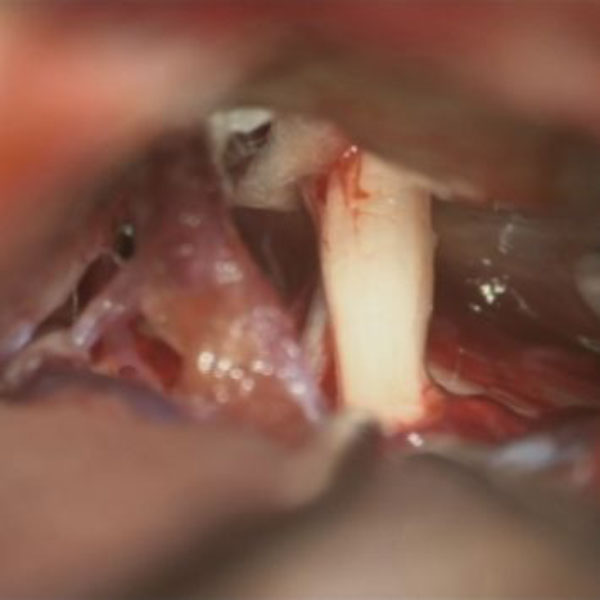

手術中

処置前

処置後